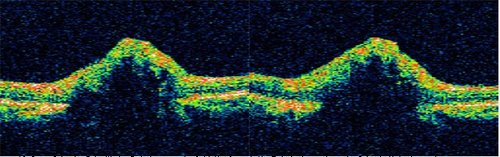

OCT所见可见视盘区扫描表面突起,回声反射较强,遮挡下方组织回声,未见视盘的视杯凹陷。